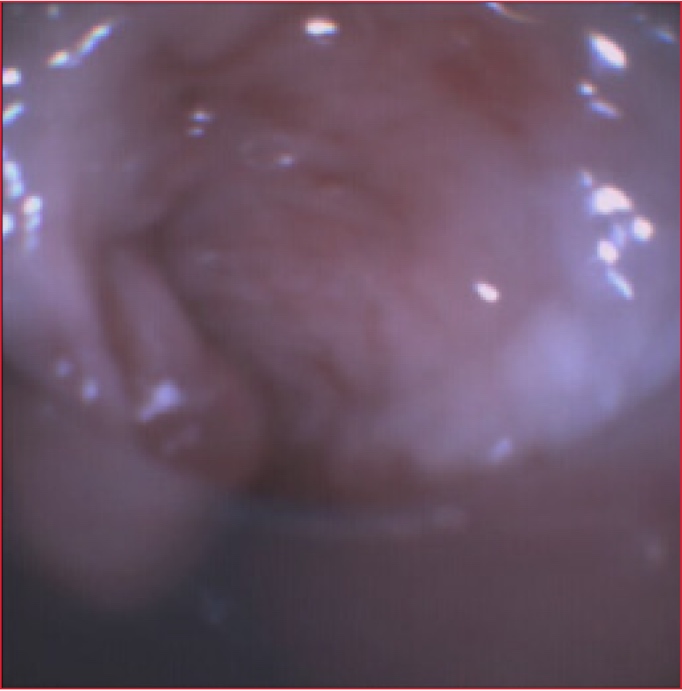

Se presenta una paciente con shock séptico secundario a neumonía de la comunidad que requirió intubación endotraqueal y ventilación mecánica, que presentó dos fallas de extubación por estridor inspiratorio; que motivó la realización de una traqueostomía. Posteriormente se evaluó la vía aérea mediante broncoscopía donde se observó una pseudomembrana, que ejercía un mecanismo valvular que obstruía, el extremo distal de la cánula de traqueostomía, se decidió extraer la cánula y asegurar la vía aérea mediante intubación endotraqueal.

A las 48 horas se repite el estudio broncoscópico que no evidenció pseudomembranas residuales.

El diagnóstico de la pseudomembrana traqueal a través de la exploración endoscópica de la vía aérea fue determinante para que la paciente fuera extubada con éxito.